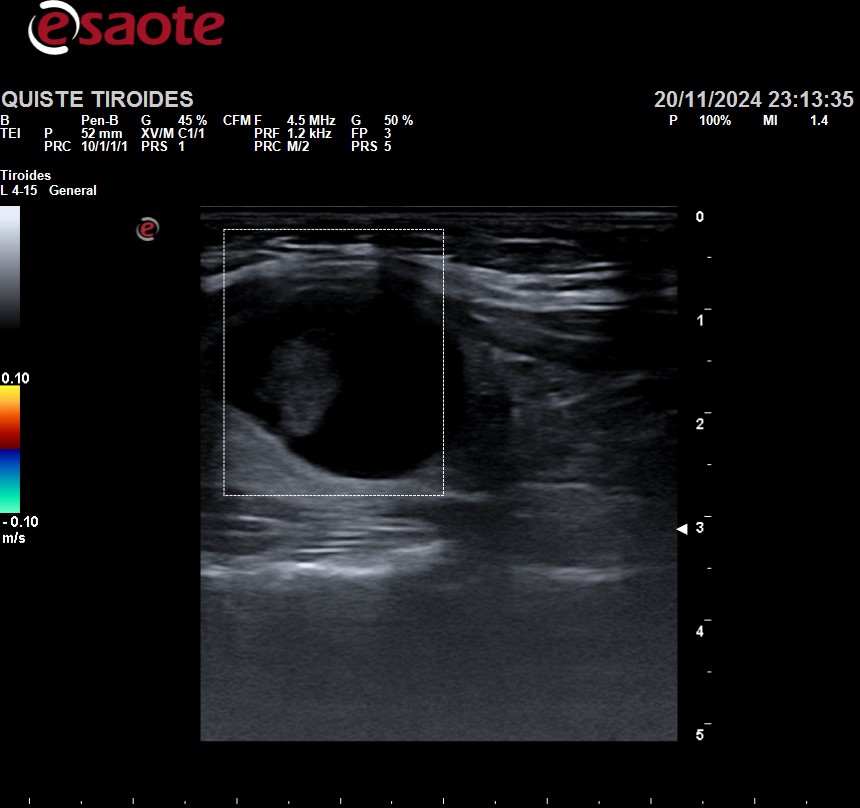

Ante dichos hallazgos, se realiza ecografía clínica tiroidea, observándose lóbulo tiroideo izquierdo sin alteraciones, y en lóbulo tiroideo derecho se observa una lesión anecoica de paredes lisas, con mínimo contenido en su interior heterogéneo, sin captación de Doppler, de unos 3cm de diámetro. No se visualizan adenopatías circundantes.

Al tratarse de un nódulo tiroideo TIRADS 1, de características benignas, y con análisis anodinos, fue dada de alta con cita en consultas de Endocrinología, para realizar seguimiento y valorar si fuera necesario drenaje del quiste.